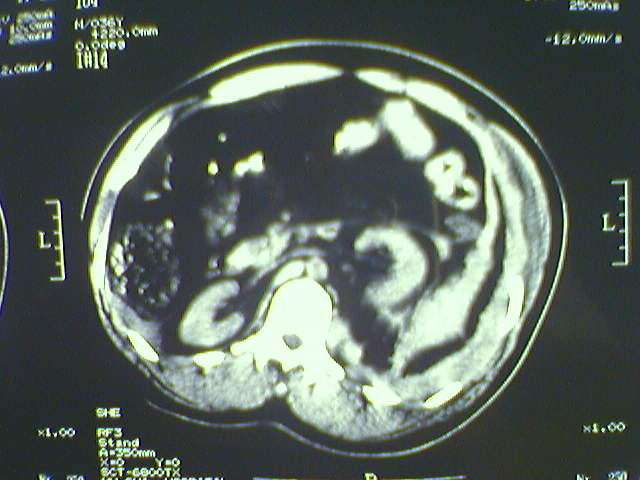

以下是引用zjzjr在2008-6-3 21:01:00的发言:[br]腹腔积液+邻近软组织肿厚.考虑感染性病变可能性大.